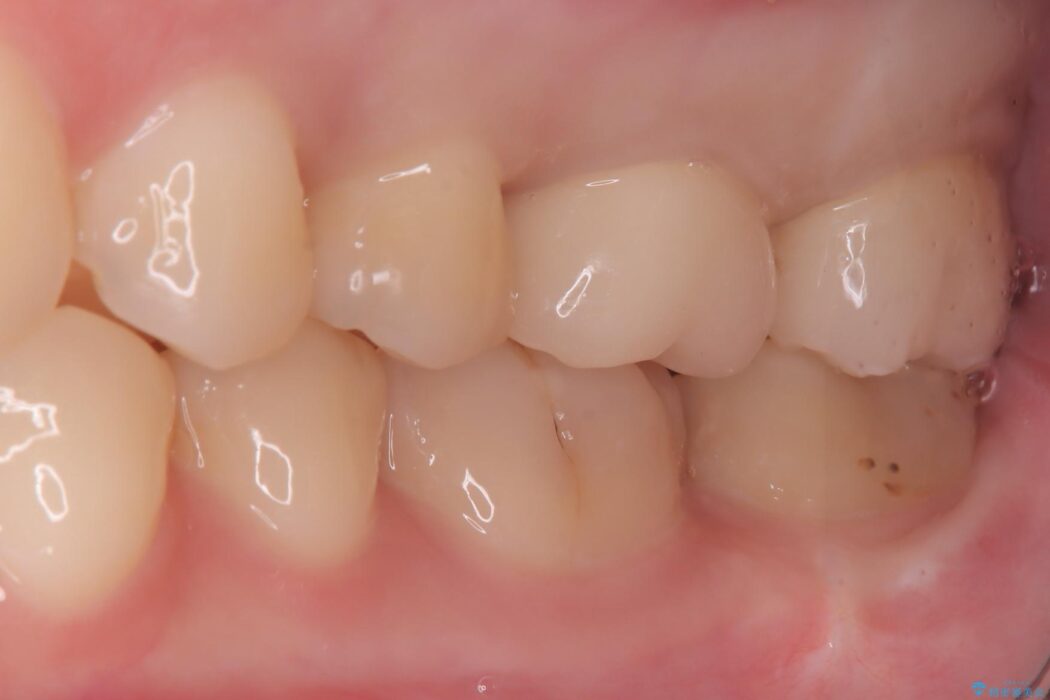

セラミックによる修復: 最終的な補綴物にはセラミックを使用しました。高い適合性により、二次的な虫歯のリスクを抑えつつ、天然歯のような自然な咬み心地と美しさを再現しました。

セラミック治療の注意事項(リスク・副作用など)

- 天然歯を削ります

- 硬い素材は天然歯を傷つけてしまう場合があります

- かみ合わせや歯ぎしりが強すぎる方はセラミックが割れてしまう可能性があります

- 自費診療(保険適用外治療)となります